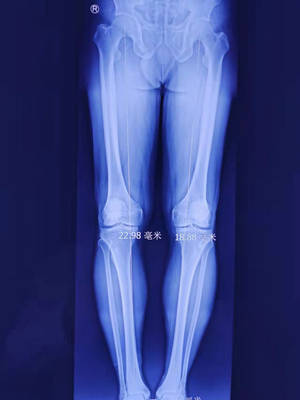

术前x光

关节科邱东新医生查看X光片,发现其为双侧膝关节炎,又结合张师傅行走步态,发现他膝关节已经出现内翻畸形。鉴于张师傅才50岁,为保障他以后的生活,建议他应该首选保膝手术,为了不影响日常生活,手术团队讨论后决定先为其左膝采用关节镜探查、机器人精准定位胫骨截骨术。